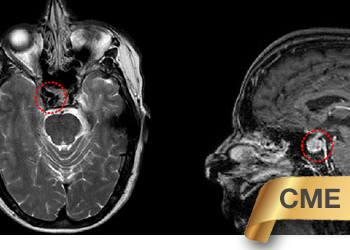

Endovascular:

CME:

Symptomatic Near-Occlusion of the Carotid Artery

Author: Jonathan L. Brisman M.D., F.A.C.S., Read More!

Right Vertebral Artery Compression Syndrome

Author: Artem Y. Vaynman M.D., F.A.A.N.S., F.A.C.S., Read More!

Brain:

74 Year Old Woman with Occipital Headaches

Author: Michael Brisman M.D., F.A.C.S., Read More!

Direct Carotid Cavernous Fistula (CCF)

Brain Metastasis